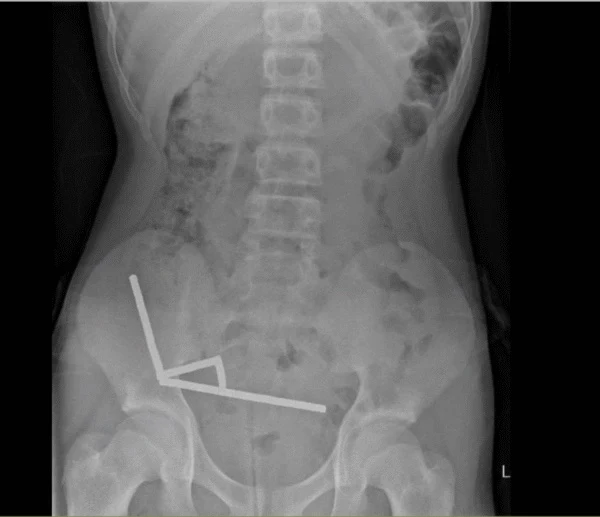

13-letni chłopiec z Nowej Zelandii trafił do szpitala z pozornie zwykłym bólem brzucha. Kiedy jednak przyznał, że połknął "ze sto magnesów", lekarze z Tauranga Hospital natychmiast zlecili prześwietlenie. I zdecydowanie nie spodziewali się tego, co na nim zobaczyli. We wnętrznościach nastolatka znajdowały się cztery długie łańcuchy neodymowych kulek, jakieś 200 sztuk!

Naukowcy zdecydowali się opisać na łamach The New Zealand Medical Journal wyjątkowy przypadek medyczny, a mowa o pewnym 13-latku z Nowej Zelandii, który połknął blisko 200 magnesów neodymowych. Kiedy zaczął się źle czuć i skarżyć na ból brzucha, rodzice natychmiast zabrali go do szpitala - tam okazało się, co jest przyczyną problemów.

Po dostaniu się do jamy brzusznej metalowe kulki zaczęły się wzajemnie przyciągać przez ściany jelit. Skutkiem było odcięcie dopływu krwi do tkanek i rozwój tzw. martwicy uciskowej - procesu, w którym fragmenty jelita dosłownie obumierają. Chirurdzy musieli więc usunąć ich część, by uratować życie chłopca.